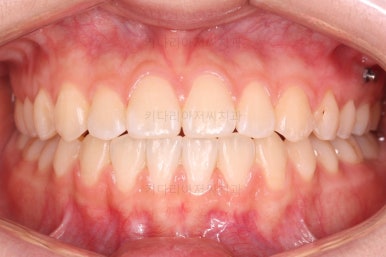

부산치아교정잘하는곳 키다리아저씨치과에서 치료한 이번 환자분의 전후 비교입니다.

왼쪽이 치료 전, 오른쪽이 치료 후 모습입니다.

덧니가 가지런해졌고 교합이 좋아졌으며 중앙선도 잘 맞아졌어요.